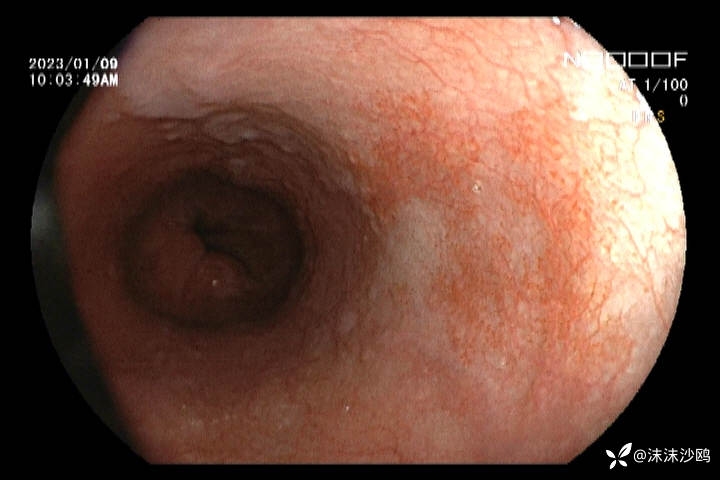

21年内镜

22年第二次是在上级医院检查并取了活检,没有大问题(我没见到病检结果。